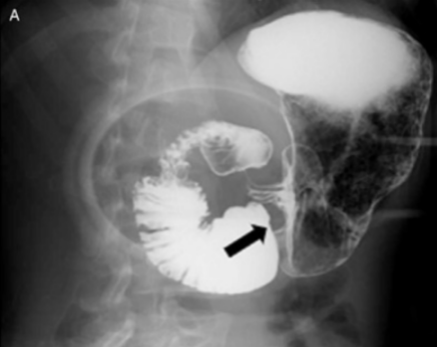

临床表现多见于瘦长体型,女性多见,急性表现为十二指肠梗阻症状与体征,慢性表现为长期腹痛、早饱、厌食和呕吐,体位变化影响,仰卧位加重,俯卧、膝胸位或左侧位缓解。影像表现X线:十二指肠水平部钡剂中断呈“笔杆征”,近段肠蠕动频繁或逆蠕动,胃和近端十二指肠扩张。CT表现:评价肠系膜上动脉与腹主动脉的解剖位置、十二指肠梗阻情况;肠系膜上动脉与腹主动脉夹角减小(<22°),间距减小(<8mm);十二指肠水平部受压狭窄,以上段胃及十二指肠扩张,可见气液平面,同时通过CT增强扫描排除小肠梗阻,肿瘤,炎症及肠系膜缺血导致的巨十二指肠症。

上消化道造影图像